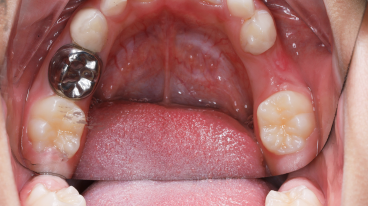

SSC (Stainless Steel Crown) là mão răng bằng thép không gỉ, được thiết kế sẵn với nhiều kích cỡ khác nhau, thường dùng để phục hồi răng sữa đã bị sâu lớn hoặc tổn thương nặng. Đây là một dạng phục hình toàn phần bao phủ toàn bộ thân răng, giúp bảo tồn và duy trì chức năng của răng sữa cho đến khi thay răng vĩnh viễn.

Mão SSC giúp bao phủ toàn bộ thân răng, giảm nguy cơ nứt vỡ và tái nhiễm khuẩn.